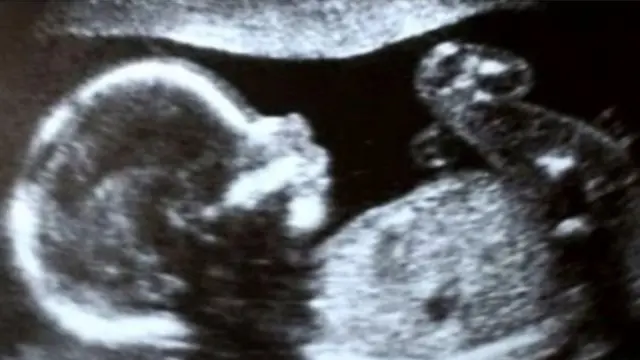

17 મહિનાથી પુણેની ગૅલેક્સી હૉસ્પિટલમાં સારવાર કરાવી રહેલાં મીનાક્ષી વાળાએ 18 ઑક્ટોબરે સીઝેરીયન થકી એક દીકરીને જન્મ આપ્યો અને એક જ દિવસમાં તે દેશભરમાં સિલિબ્રિટી બની ગઈ.

તેનું કારણ એ છે કે તે સંપૂર્ણ એશિયા-પ્રશાંતમાં ગર્ભાશયના ટ્રાન્સપ્લાન્ટથી જન્મેલી એ પ્રથમ બાળકી છે.

ગુજરાતના ભરૂચનાં રહેવાસી મીનાક્ષી દેશના પ્રથમ મહિલા છે, જેઓ ગર્ભાશય ટ્રાન્સપ્લાન્ટથી માતા બન્યાં છે.

રાધા 32 સપ્તાહ જ માતાના ગર્ભમાં રહી. જન્મ સમયે તેનું વજન 1.45 કિલો હતું.

રાધાનું વજન 2 કિલોનું ન થઈ જાય ત્યાં સુધી તે હૉસ્પિટલમાં જ રહેશે.